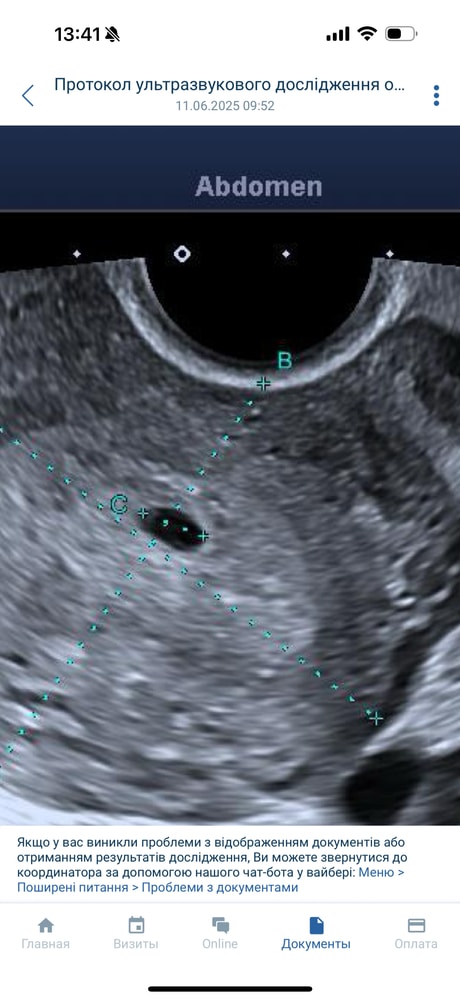

Ксения, девочки, отправили на чистку Спасибо что были со мной это время 🙏🏻 Изображение

Ксения, сказали пустое и деформированное с кровоизлиянием внутри Изображение Изображение